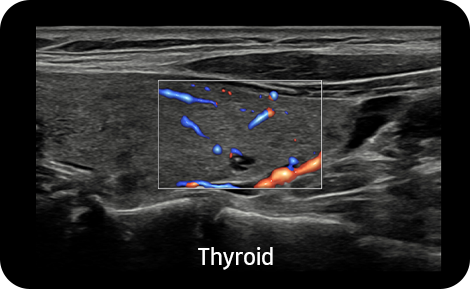

S-Flow™, směrová technologie Power Doppler, pomáhá detekovat periferní cévy. Umožňuje přesnou diagnózu v případech, kdy je vyšetření krevního průtoku velmi obtížné.